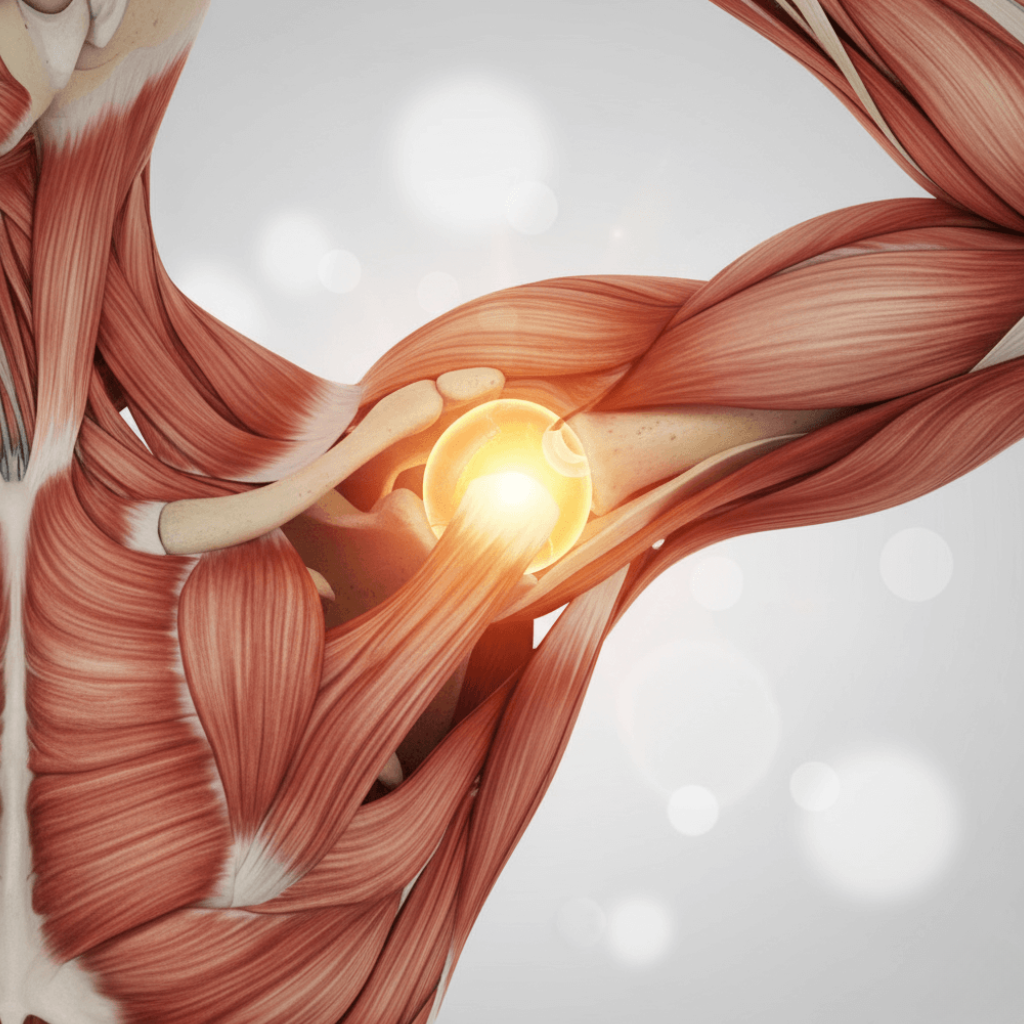

The Importance of Joints in Daily Life

Joints are essential for almost every movement we perform daily.

They connect bones, allow flexibility, and absorb impact, ensuring we can walk, run, climb stairs, stretch, and participate in physical activities safely.

When joints are healthy, mobility is preserved, which directly affects energy, disposition, and overall quality of life.

Stiff or uncomfortable joints can limit independence, make simple tasks difficult, and even affect emotional well-being.